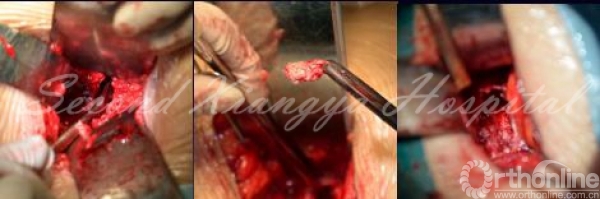

6.辅以头灯放大镜,或者显微镜,直视下用刮匙、髓核钳等器械可有效摘除突出髓核(非游离型)。先以刀片切除前外侧纤维环,以Cobb剥离器沿终板剥离椎间盘,髓核钳夹出,直至椎体后缘。以椎体间撑开器撑开椎间隙,用刮匙去除附着在椎体后缘的纤维环,可见纤维环右侧有破口,以神经剥离子勾出脱出的髓核,枪式椎板咬骨钳修正后缘增厚的纤维环后进一步探查椎管内有无残留髓核组织,但注意不要过度在椎管内操作防止出血。减压完成后,可见反光的硬膜囊前部。

显微镜操作

镜下图片

显微镜下髓核摘除视频